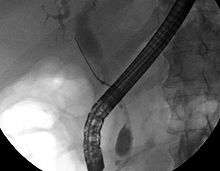

Imaging of the biliary tree

While abdominal imaging can be useful in the diagnosis of cholangiocarcinoma, direct imaging of the bile ducts is often necessary. Endoscopic retrograde cholangiopancreatography (ERCP), an endoscopic procedure performed by a gastroenterologist or specially trained surgeon, has been widely used for this purpose. Although ERCP is an invasive procedure with attendant risks, its advantages include the ability to obtain biopsies and to place stents or perform other interventions to relieve biliary obstruction.[7] Endoscopic ultrasound can also be performed at the time of ERCP and may increase the accuracy of the biopsy and yield information on lymph node invasion and operability.[47] As an alternative to ERCP, percutaneous transhepatic cholangiography (PTC) may be utilized. Magnetic resonance cholangiopancreatography (MRCP) is a non-invasive alternative to ERCP.[48][49][50] Some authors have suggested that MRCP should supplant ERCP in the diagnosis of biliary cancers, as it may more accurately define the tumor and avoids the risks of ERCP.[51][52][53]